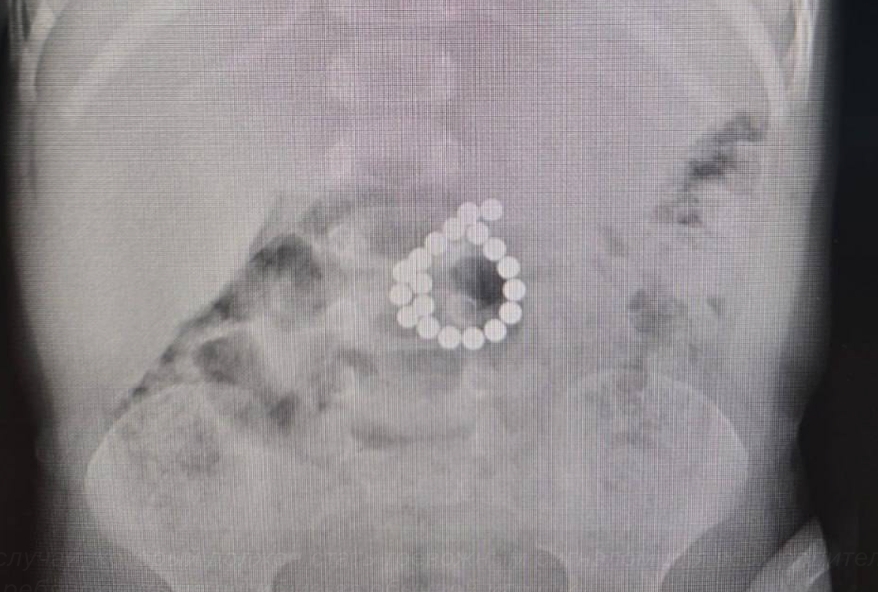

Во время срочной операции хирурги нашли в кишечнике мальчика 19 магнитов и две дыры. Все чужеродные предметы были извлечены, а повреждения зашиты. После хирургического вмешательства ребенок провел шесть дней в реанимации, где ему оказывали интенсивную помощь, включая введение питательных веществ внутривенно, антибиотики и обезболивание, пишет ugra-news.ru.